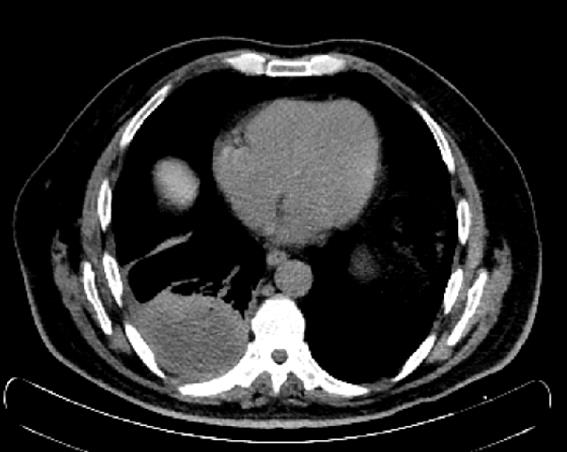

El TC de tórax permite confirmar las imágenes de Rx, caracterizarlas y localizarlas. Es una técnica rápida, indolora y precisa. Permite obtener imágenes de huesos, tejidos blandos y vasos sanguíneos al mismo tiempo, teniendo la capacidad de detectar nódulos muy pequeños, exceso de fluido alrededor de los pulmones (derrame pleural) o enfisema, entre otros. El TC es menos sensible al movimiento de pacientes que la RMN y puede realizarse aunque el paciente tenga implantado cualquier tipo de dispositivo médico. Además, podemos limitar el rango de densidades en función de la estructura que queramos analizar, encontrando, en la radiología torácica, dos ventanas básicas: pulmonar y mediastínica.